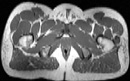

Visible Human male: Sectio transversalis 1921

CT

NMR

Pd                          / T2 \                         T1